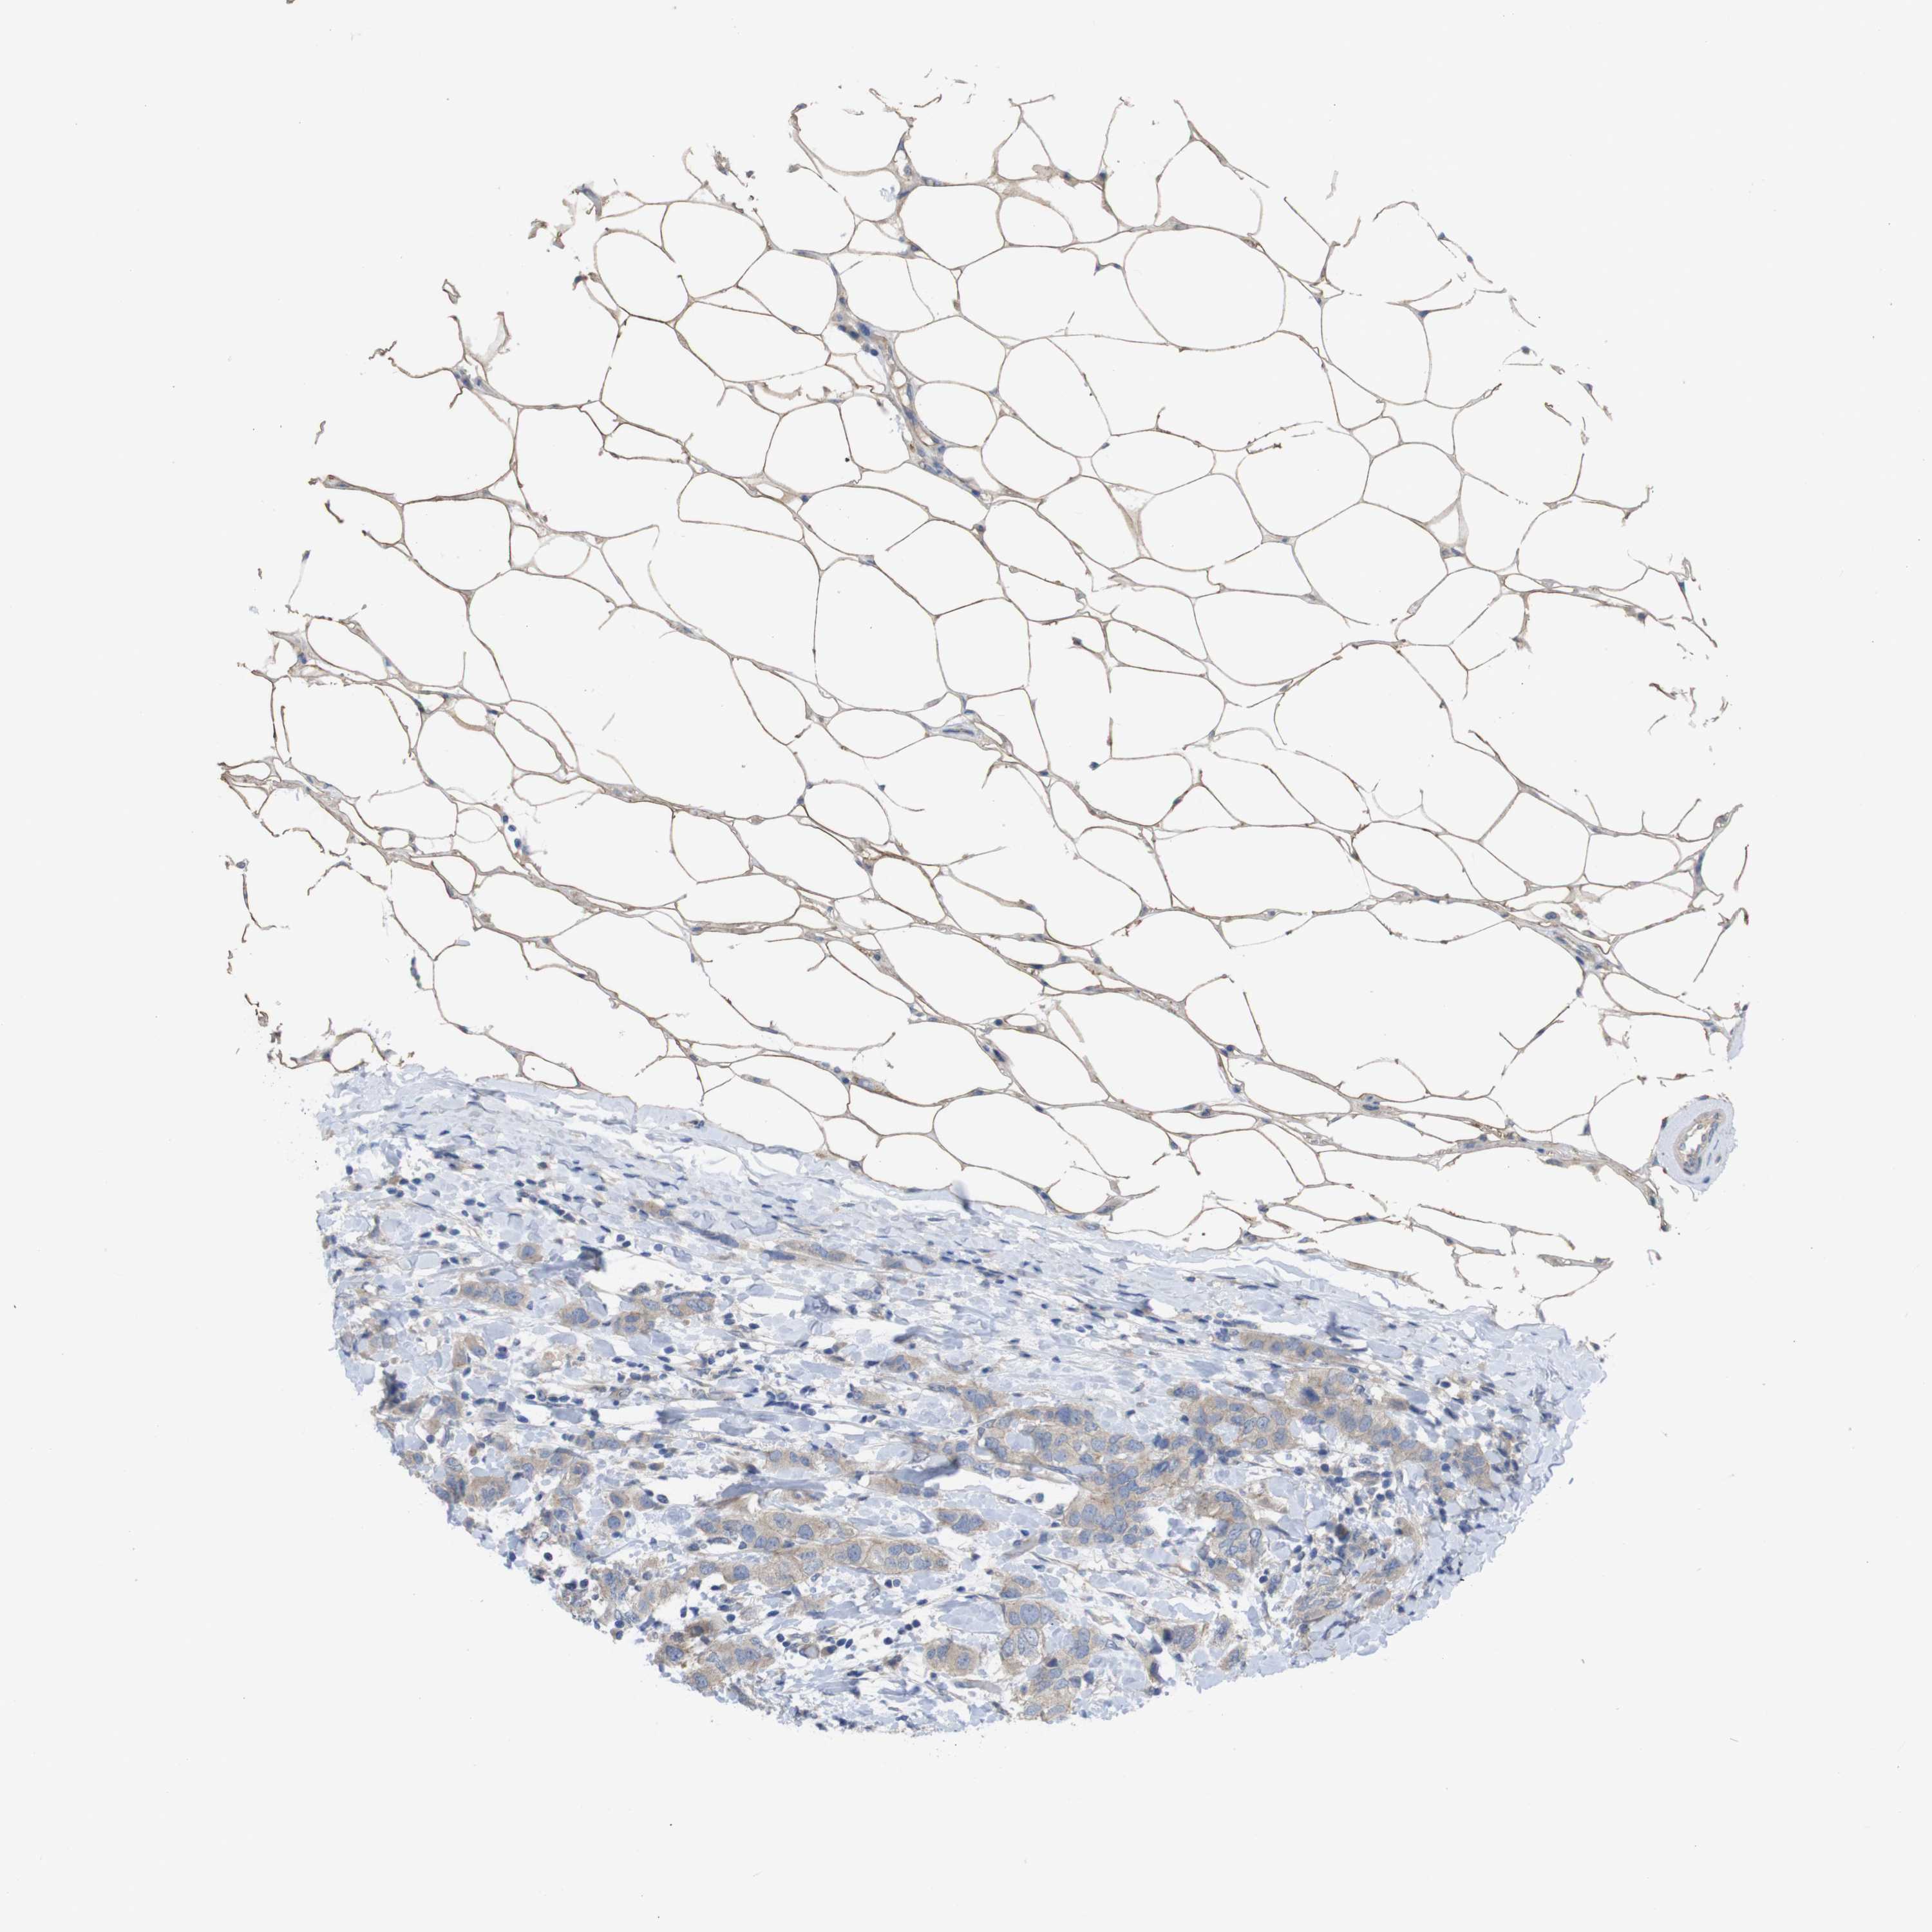

CANCER BREAST CANCER Show tissue menu

BRCA TCGA BRCA VALIDATION PROTEIN EXPRESSION